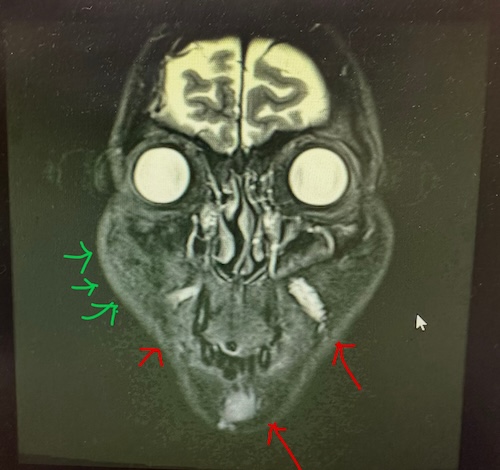

症例は30代女性。2年前に頬にFGF添加PRP注射を受け、その1年後から頬の膨隆を認めました。

しこりが大きくなるため当院受診されました。

赤矢印:過去のヒアルロン酸注入

緑矢印:PRP+FGF注入後のしこり

炎症反応及び繊維化した硬い組織と液体成分を認める

このMRIは、顔を輪切りにした断面画像です。丸く白く写っているのが眼球で、その下に

- 皮膚

- 皮下脂肪

- 筋肉

- 注入された物質や、その影響を受けた組織

がミルフィーユ状に重なって存在しています。MRIは、水分の多さ・組織の硬さ・構造の乱れを写し分ける検査です。

赤矢印:ヒアルロン酸注入後の状態

赤い矢印で示されている部分は、ヒアルロン酸注入の影響が残っている部位です。

この部分の特徴は、

・比較的はっきりした形

・周囲と区別できる

・白っぽく、水分を含んだ信号

・一部が丸く、かたまり状

これは、

ヒアルロン酸(=水分を抱え込むジェル状物質)が、局所に留まっている状態を示しています。

緑:FGF添加PRP注入後の状態

緑の矢印で示している部分は、FGFを加えたPRP注入後の変化と考えられる領域です。

この部分は画像上から以下が読み取れます。

・皮膚のすぐ下に広く存在している

・境界がはっきりせず、ぼやけている

・ベタッと面状に広がっている

・周囲の組織と混ざり合うように写っている

これは、注入した液体がそのまま残っている状態というよりも、PRPをきっかけに体が反応し、炎症と修復が起こった結果、組織そのものが変化した状態を示唆します。

その過程で、

・組織が少し厚く、硬くなる(繊維化)

・同時に、むくみのような水分が組織の中に残る

ということが起こる場合があります。

MRIでは、硬さを示す部分と、水分を含む部分が混ざって写るため、このように「境界がはっきりしない、広がる変化」として見えます。この状態では、

これは、硬くなった組織の中に、液体成分(リンパ液など)が混ざっている状態と、画像の所見が一致しています。